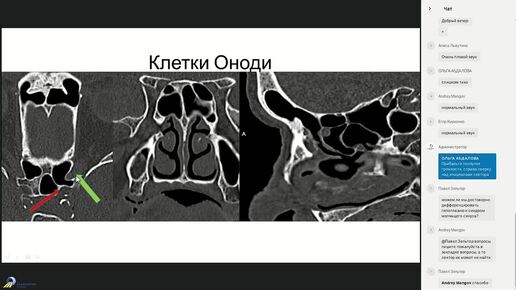

Лучевая Анатомия придаточных пазух носа 2